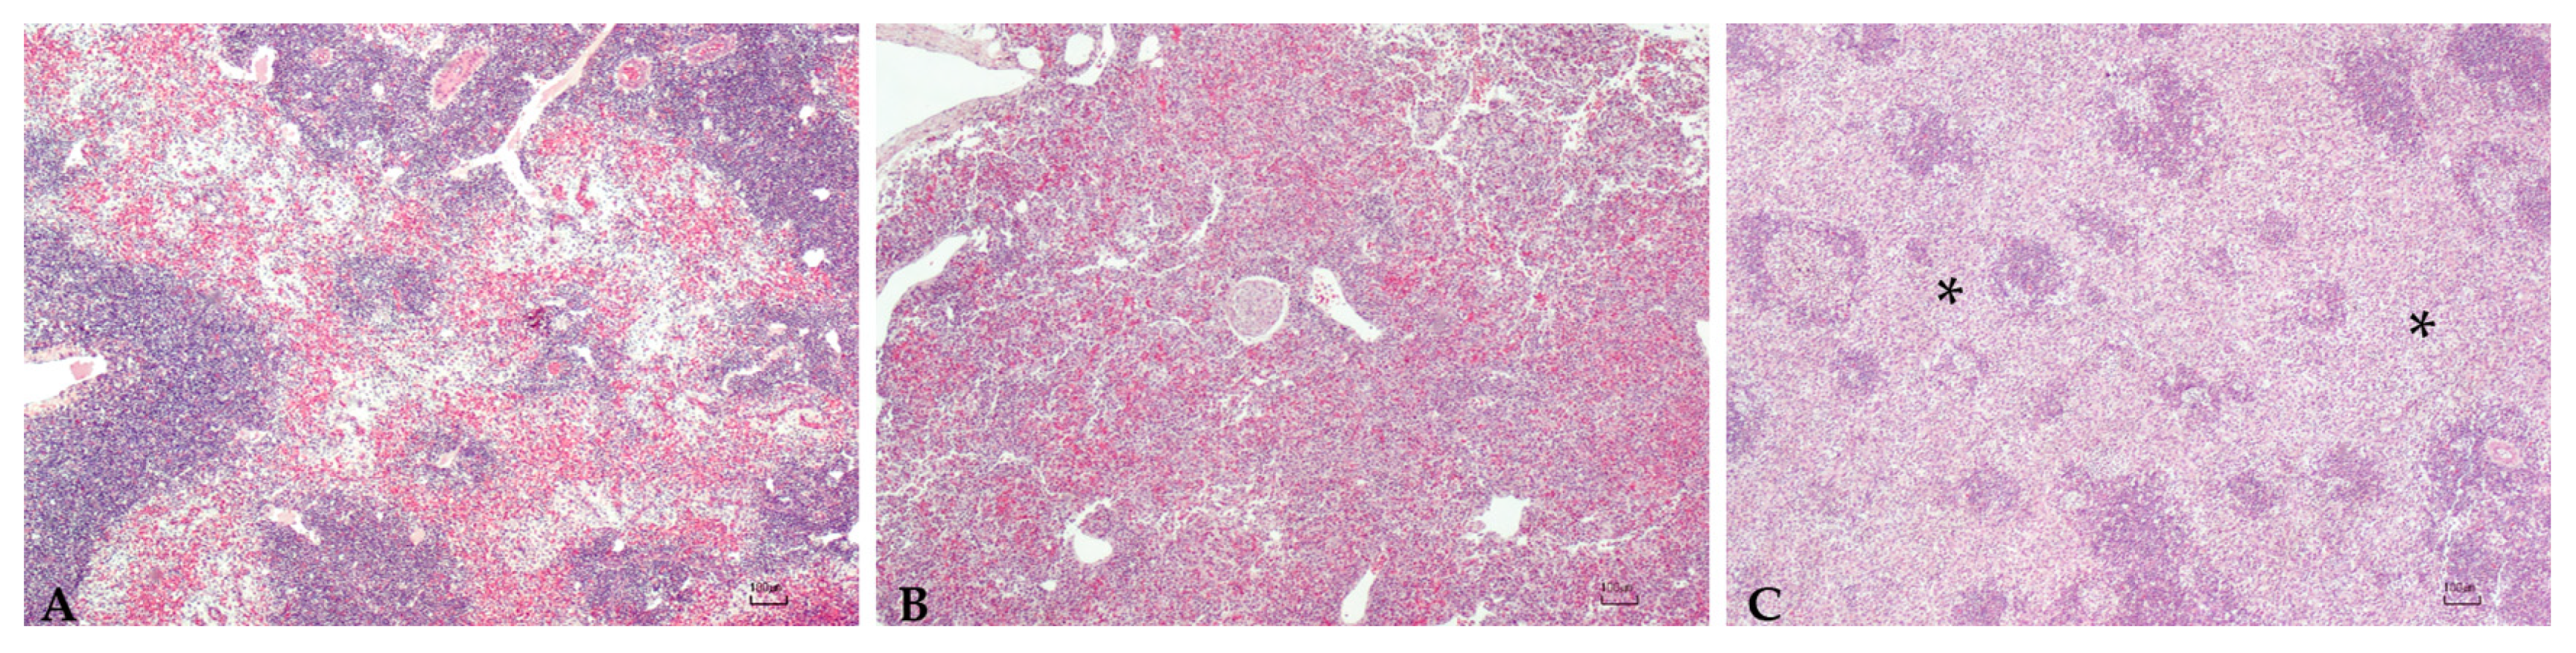

3.5. Histopathology

| ID | Liver | Spleen | Gut |

|---|---|---|---|

| 78697.1 | Severe inflammation | Severe inflammation | Severe inflammation |

| 78697.2 | Moderate inflammation | Mild inflammation/severe congestion | Mild inflammation |

| 78697.3 | Mild inflammation/severe congestion | Moderate inflammation | No lesion |

| 78697.4 | Moderate inflammation | No lesion | No lesion |